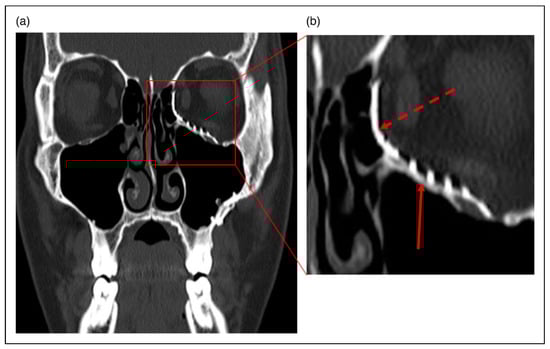

Case 1